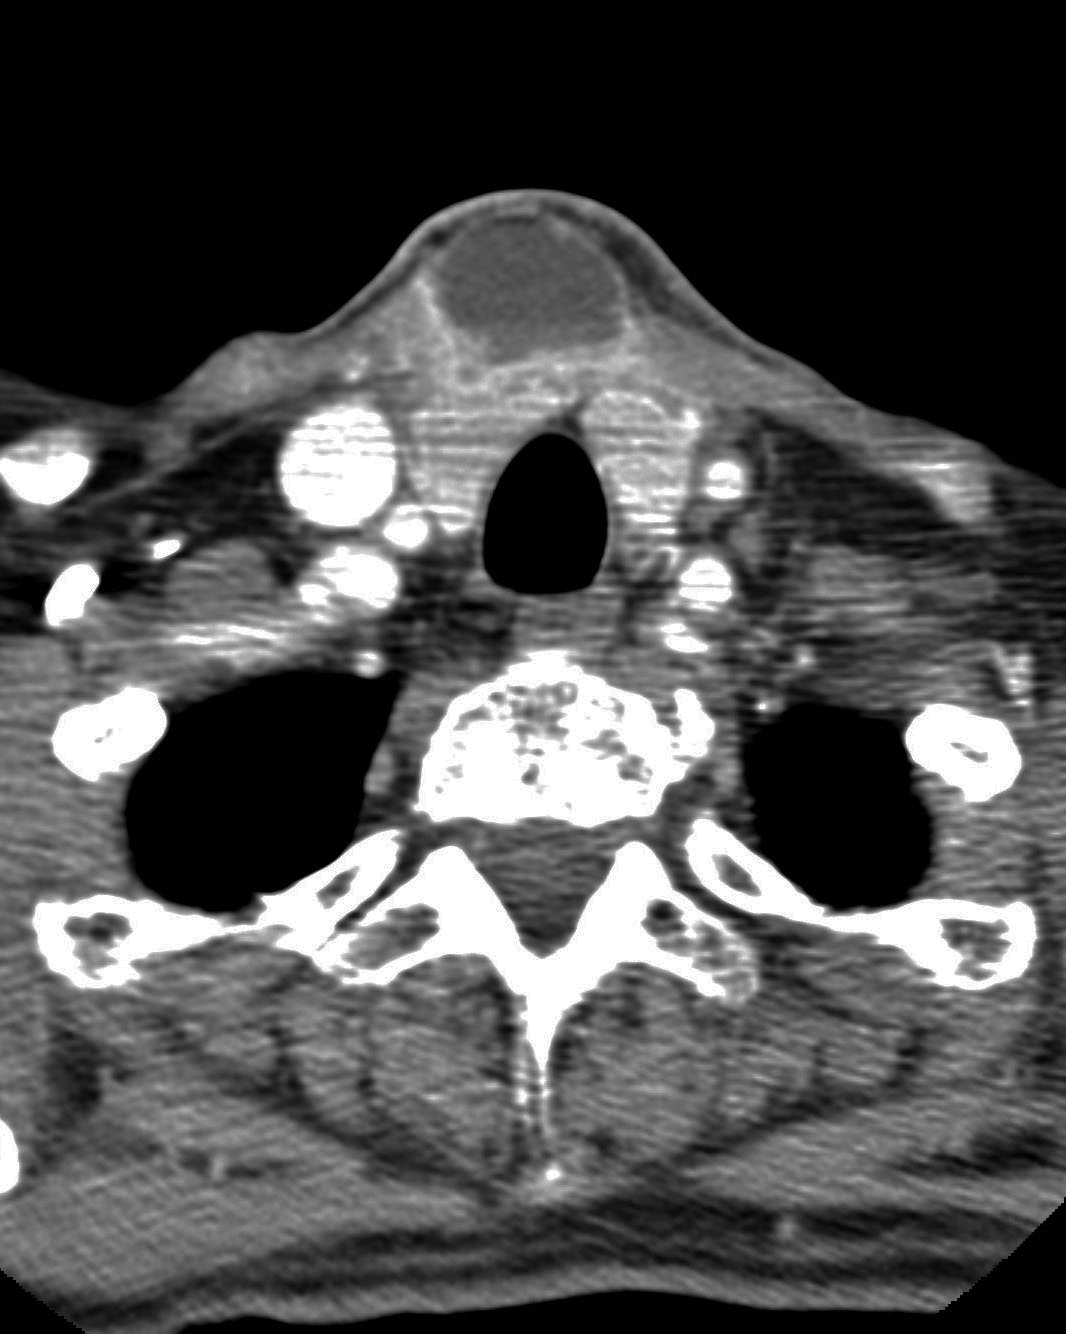

• CT es más accesible que las anteriores y proporciona información anatómica detallada, particularmente útil para evaluar la implicación ósea y la planificación quirúrgica. Es más rápida y accesible que la MRI y la PET/CT, pero implica radiación ionizante y puede tener menor sensibilidad para detectar anomalías de tejidos blandos en comparación con la MRI. Como ejemplo, en la Figura 1 se ilustra una imagen de tomografía computerizada de un cancer de larigne de células escamosas.

Figure 1: Imagen axial obtenida mediante tomografía computarizada (CT) del cuello. En particular, en esta imagen se visualiza un cáncer de laringe que dio lugar a metástasis. Esta imagen fue obtenida de radiopedia.org.